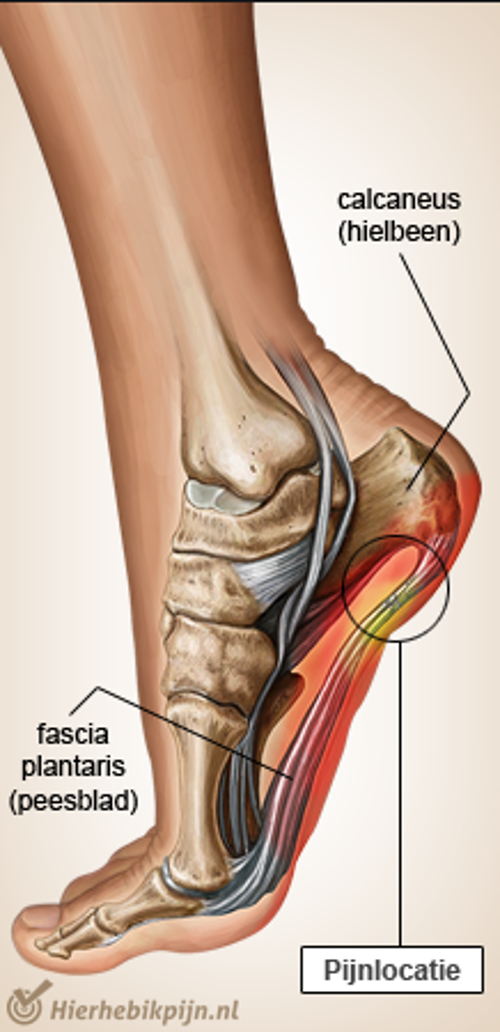

- Op de pijnlijke plek onder uw voet druk zetten met een (tennis)balletje of een flesje (ijs)water. Zie Figuur 2.